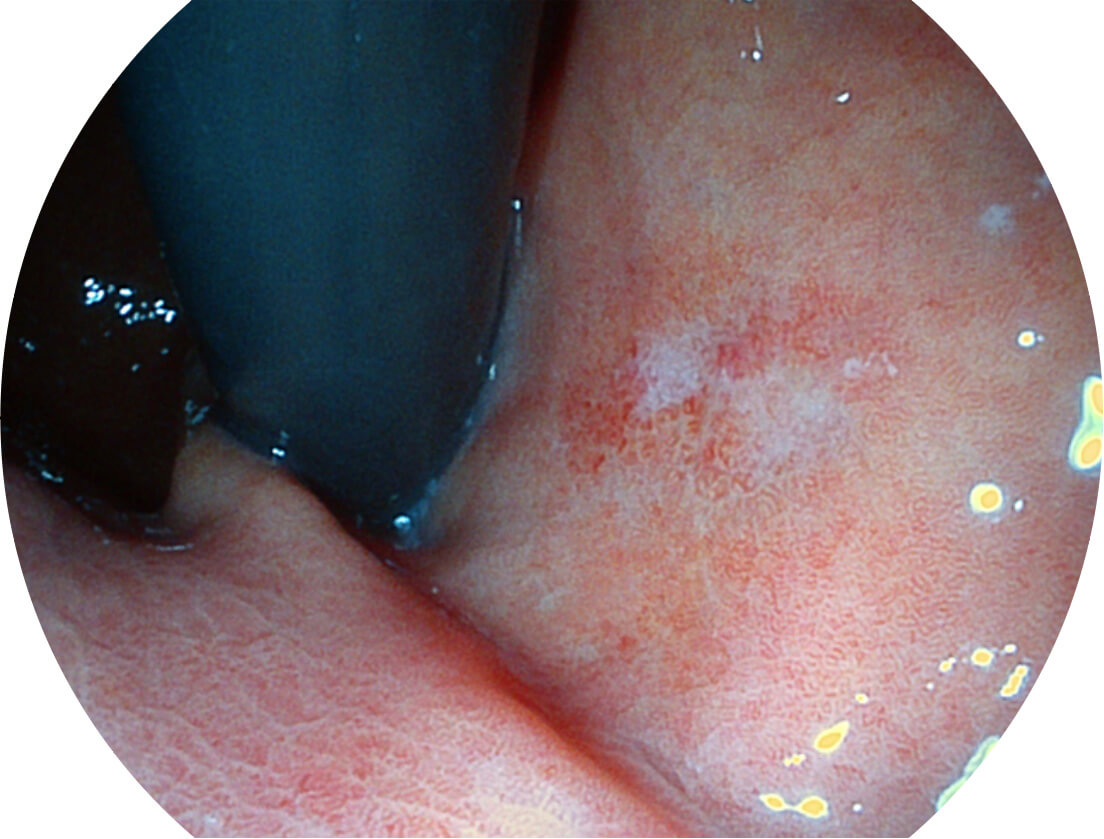

白光图像

VIST图像

强调浅层黏膜结构的同时,保证照明亮度和提升浅层微血管与中层血管颜色对比度,病变边界更清晰。

采用光路合束技术,光谱自由度高,实现了更丰富的照明模式,染色模式SFI及VIST,从远景到近景,助力消化道早期疾病诊断。